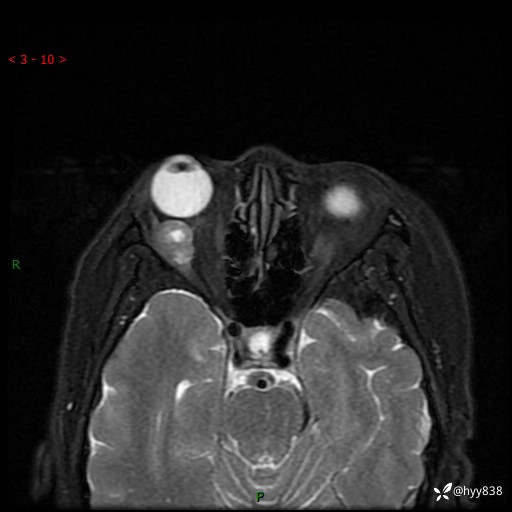

老年女性,右眼球突出1月。说说鉴别诊断,看谁第一个秒---(有结果)

主诉:发现右眼球突出1月余

简要病史:患者于1月前无明显诱因发现右眼球突出,偶感磨痛、眼胀,无视力下降,无头痛,恶心呕吐等不适。10天前就诊于当地县人民医院就诊,完善头颅ct检查,诊断为右侧眼眶肿物,建议患者上级医院进一步治疗,患者因个人原因拒绝。拟行手术,来我院就诊,门诊行相关检查后以“右眼眼眶肿物”收入院。 患病以来,患者精神饮食睡眠尚可,大小便如常、体重无明显改变。

辅助检查:MRI

临床诊断:眼眶肿物

眼眶MRI平扫+增强